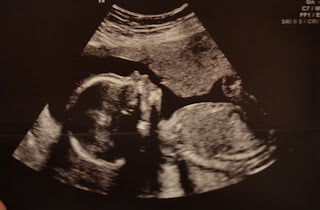

20 weeks!

Today was one of my favorite days - the 20 week ultrasound! I love this day because it's such an amazing experience. I am so grateful to God for this precious child. Unfortunately, I know what it's like to stare at an ultrsound screen desperate for any sign of life only to leave the room in tears so any time I get to watch a living, moving, healthy creation, it's pure joy. All of those hours I've spent nauseated and hanging my head over a toilet just completely disappear.

The baby is healthy. Amazing. I was worried throughout the ultrasound because she kept going back to look at the baby's heart, and I didn't see the clear cut 4 chambers I'd seen with my 2 previous babies. In the end they said everything looked perfect. I'm obviously not a sonographer so I trust that she and the doctor know what they were looking at and that the baby's heart is perfectly fine.

Throughout the ultrasound Number 3 constantly had his/her hand next to his face. It seemed as if Number 3 was trying really hard to figure out how to get that thumb in the mouth. We even saw during the 4D part Number 3 opening his mouth - much like a newborn that is rooting. Finally at the end of the ultrasound when they were getting the final profile shots Number 3 finally got that thumb in his mouth and started sucking away. (Apparently sonogaphers can tell when they are sucking their thumb or not --who knew??) Watching the little one's success made me laugh, which shook the baby, and the poor thing lost his thumb and was back to square one! Poor baby!